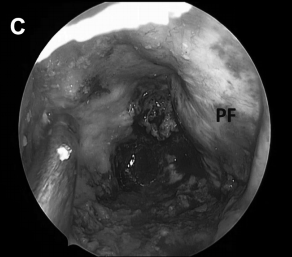

▼术中见胆固醇肉芽肿包膜,进行切除并送标本活检后,逐渐切除肿瘤病变(图6C)。

▼解剖、剥离并切除肿瘤包膜(D、E)

▼(L)使用鼻中隔瓣(NSF)完成封闭。CC,囊包膜;PFD,后颅窝硬脑膜;S,蝶鞍;T,肿瘤。